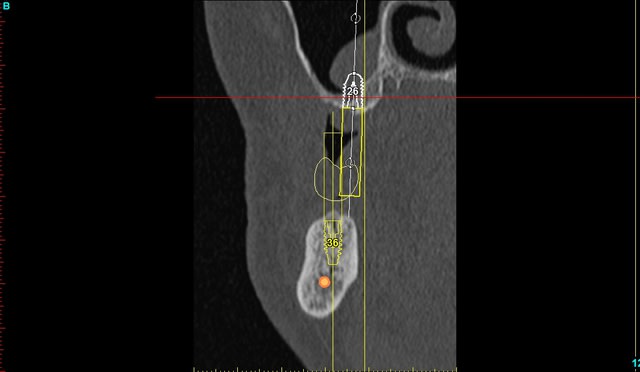

je mets les coupes et les radios post op...

intervention "quasi" flaless, juste des incisions crestales en W pour manager les papilles...